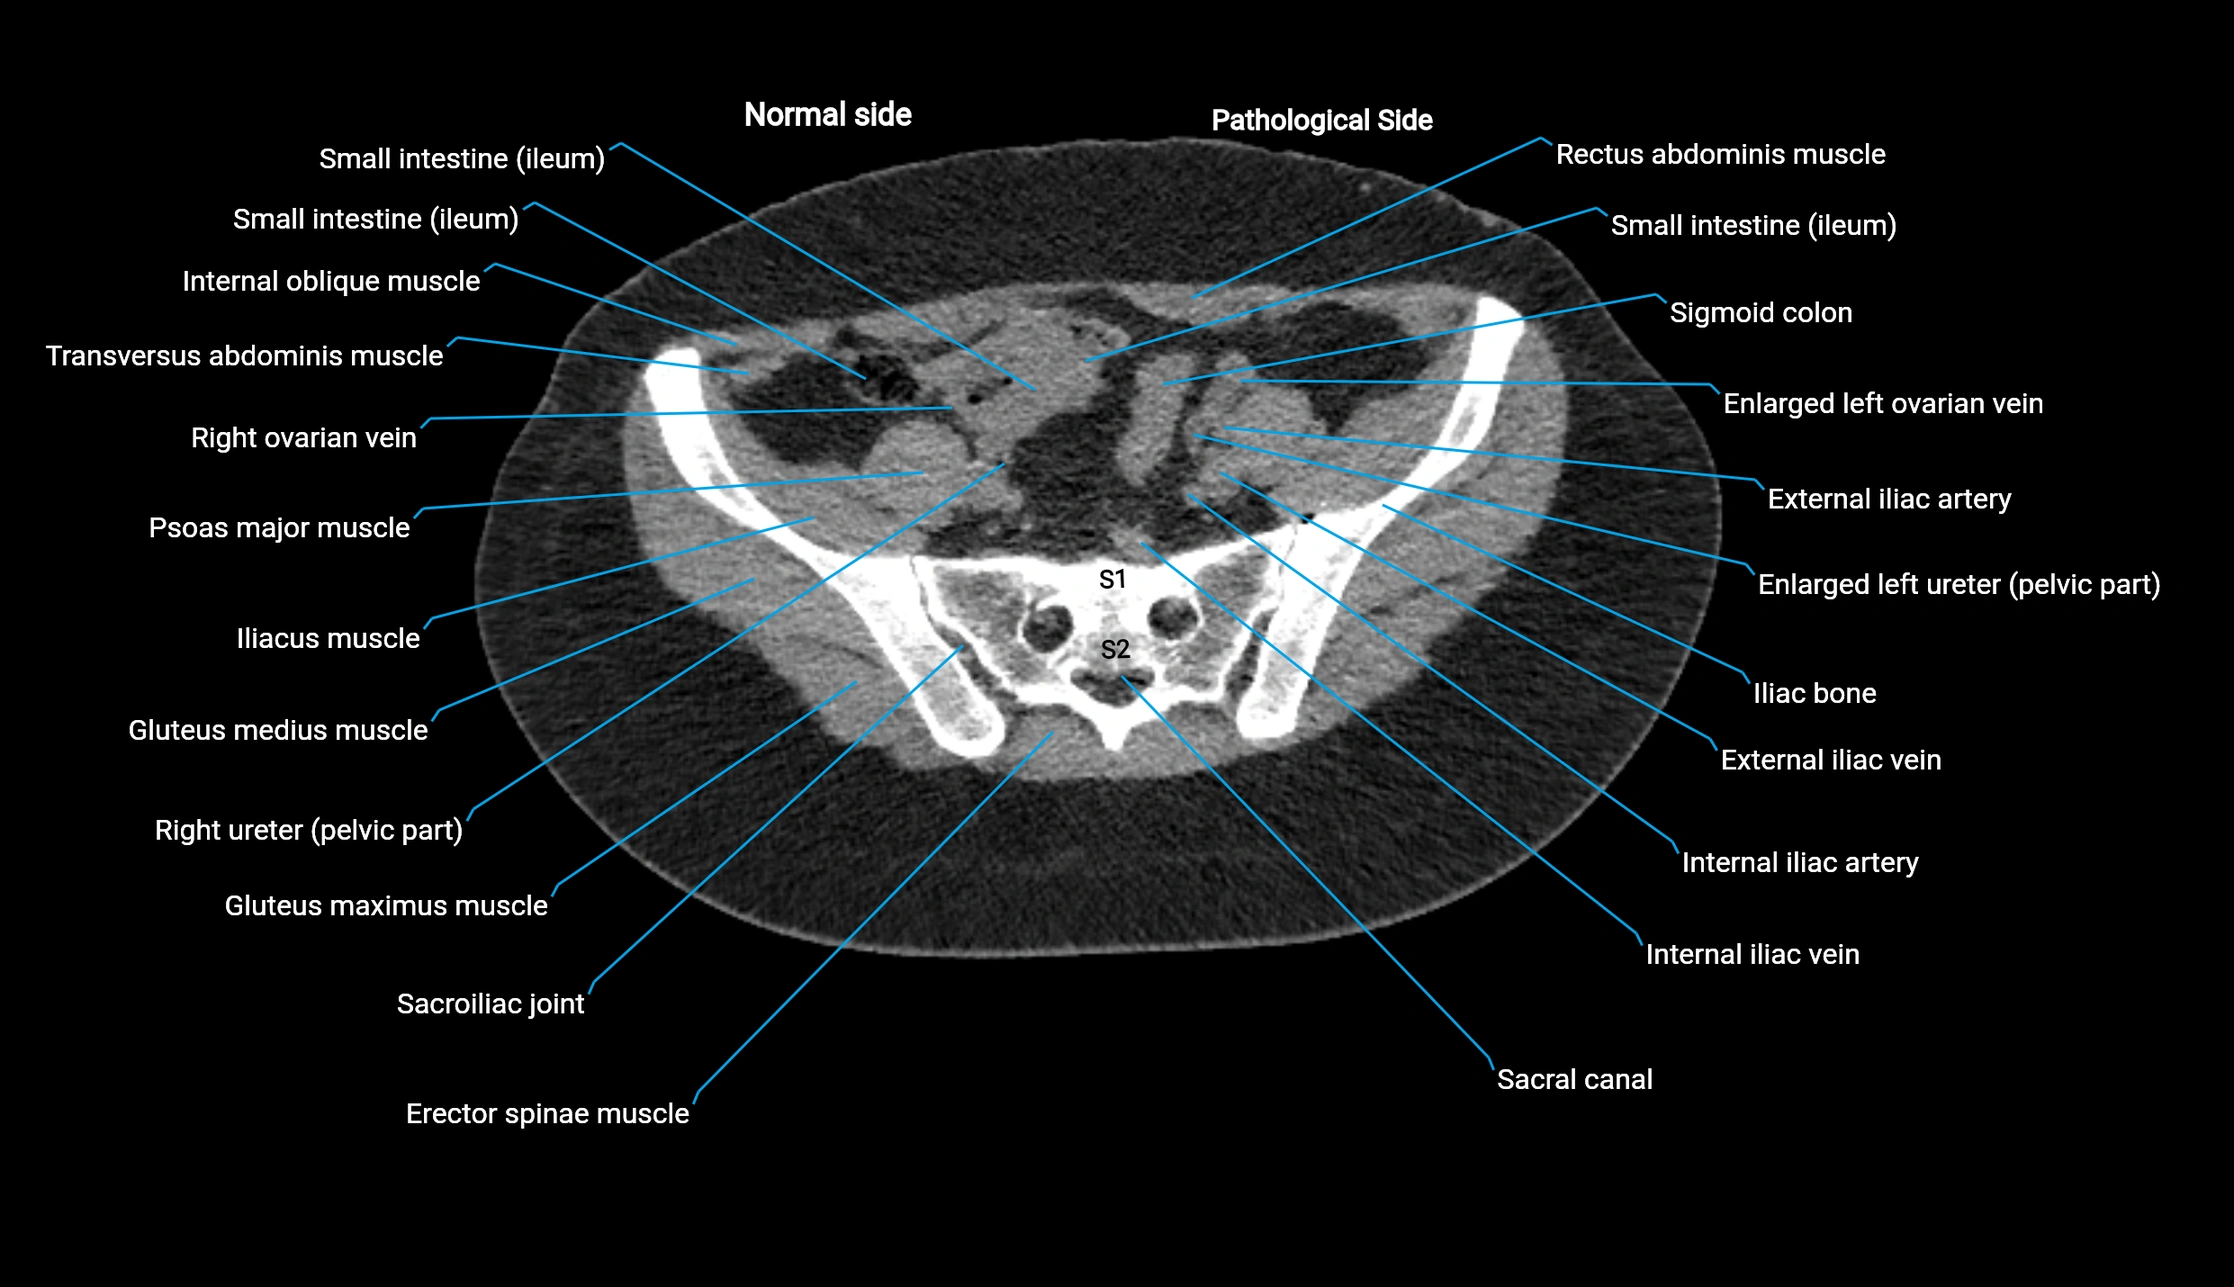

CT image

image